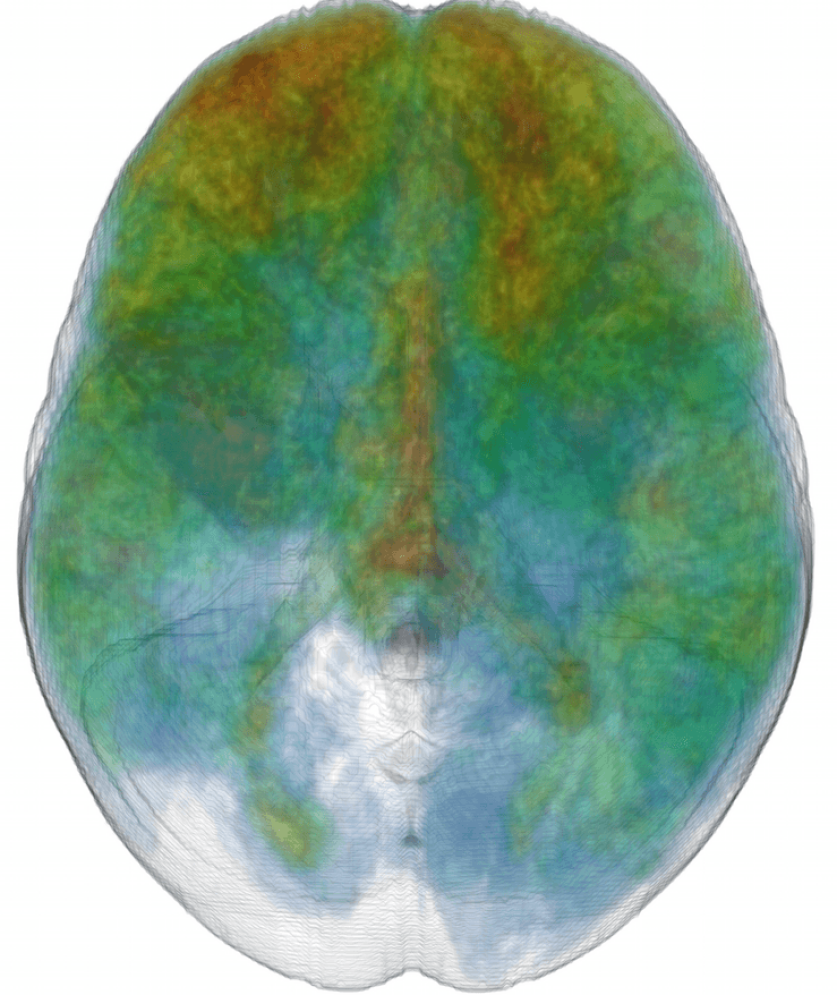

Furthermore, a detailed analysis of the network reveals valuable insights into the powerful black box of deep learning with CNNs. For example, we have found that our network is capable of learning very complex, high level features that separate gray matter (GM), cerebrospinal fluid (CSF) and other anatomical structures to identify the image regions corresponding to lesions.

The discriminative power of the learned features is indicated by the success of recent CNN-based systems in matching human performance in domains where it was previously considered too ambitious (He et al. (2015); Silver et al. (2016)). Analysis of the automatically extracted information could potentially provide novel insights and facilitate research on pathologies for which little prior knowledge is currently available. In an attempt to illustrate this, we explore what patterns have been learned automatically for the lesion segmentation tasks. We visualize the activations of DeepMedic’s FMs when processing a subject from our TBI database. Many appearing patterns are difficult to interpret, especially in deeper layers. In Fig. 14 we provide some examples that have an intuitive explanation. One of the most interesting findings is that the network learns to identify the ventricles, CSF, white and gray matter. This reveals that differentiation of tissue type is beneficial for lesion segmentation. This is in line with findings in the literature, where segmentation performance of traditional classifiers was significantly improved by incorporation of tissue priors (Van Leemput et al. (1999); Zikic et al. (2012)). It is intuitive that different types of lesions affect different parts of the brain depending on the underlying mechanisms of the pathology. A rigorous analysis of spatial cues extracted by the network may reveal correlations that are not well defined yet.

Similarly intriguing is the information extracted in the low-resolution pathway. As they process greater context, these neurons gain additional localization capabilities. The activations of certain FMs form fields in the surrounding areas of the brain. These patterns are preserved in the deepest hidden layers, which indicates they are beneficial for the final segmentation (see two last rows of Fig. 14). We believe these cues provide a spatial bias to the system, for instance that large TBI contusions tend to occur towards the front and sides of the brain (see Fig. 1(c)). Furthermore, the interaction of the multi-resolution features can be observed in FMs of the hidden layer that follows the concatenation of the pathways. The network learns to weight the output of the two pathways, preserving low resolution in certain parts and show fine details in others (bottom row of Fig. 14, first three FMs). Our assumption is that the low-resolution pathway provides a rough localization of large pathologies and brain areas that are challenging to segment, which reserves the rest of the network’s capacity for learning detailed patterns associated with the detection of smaller lesions, fine structures and ambiguous areas.